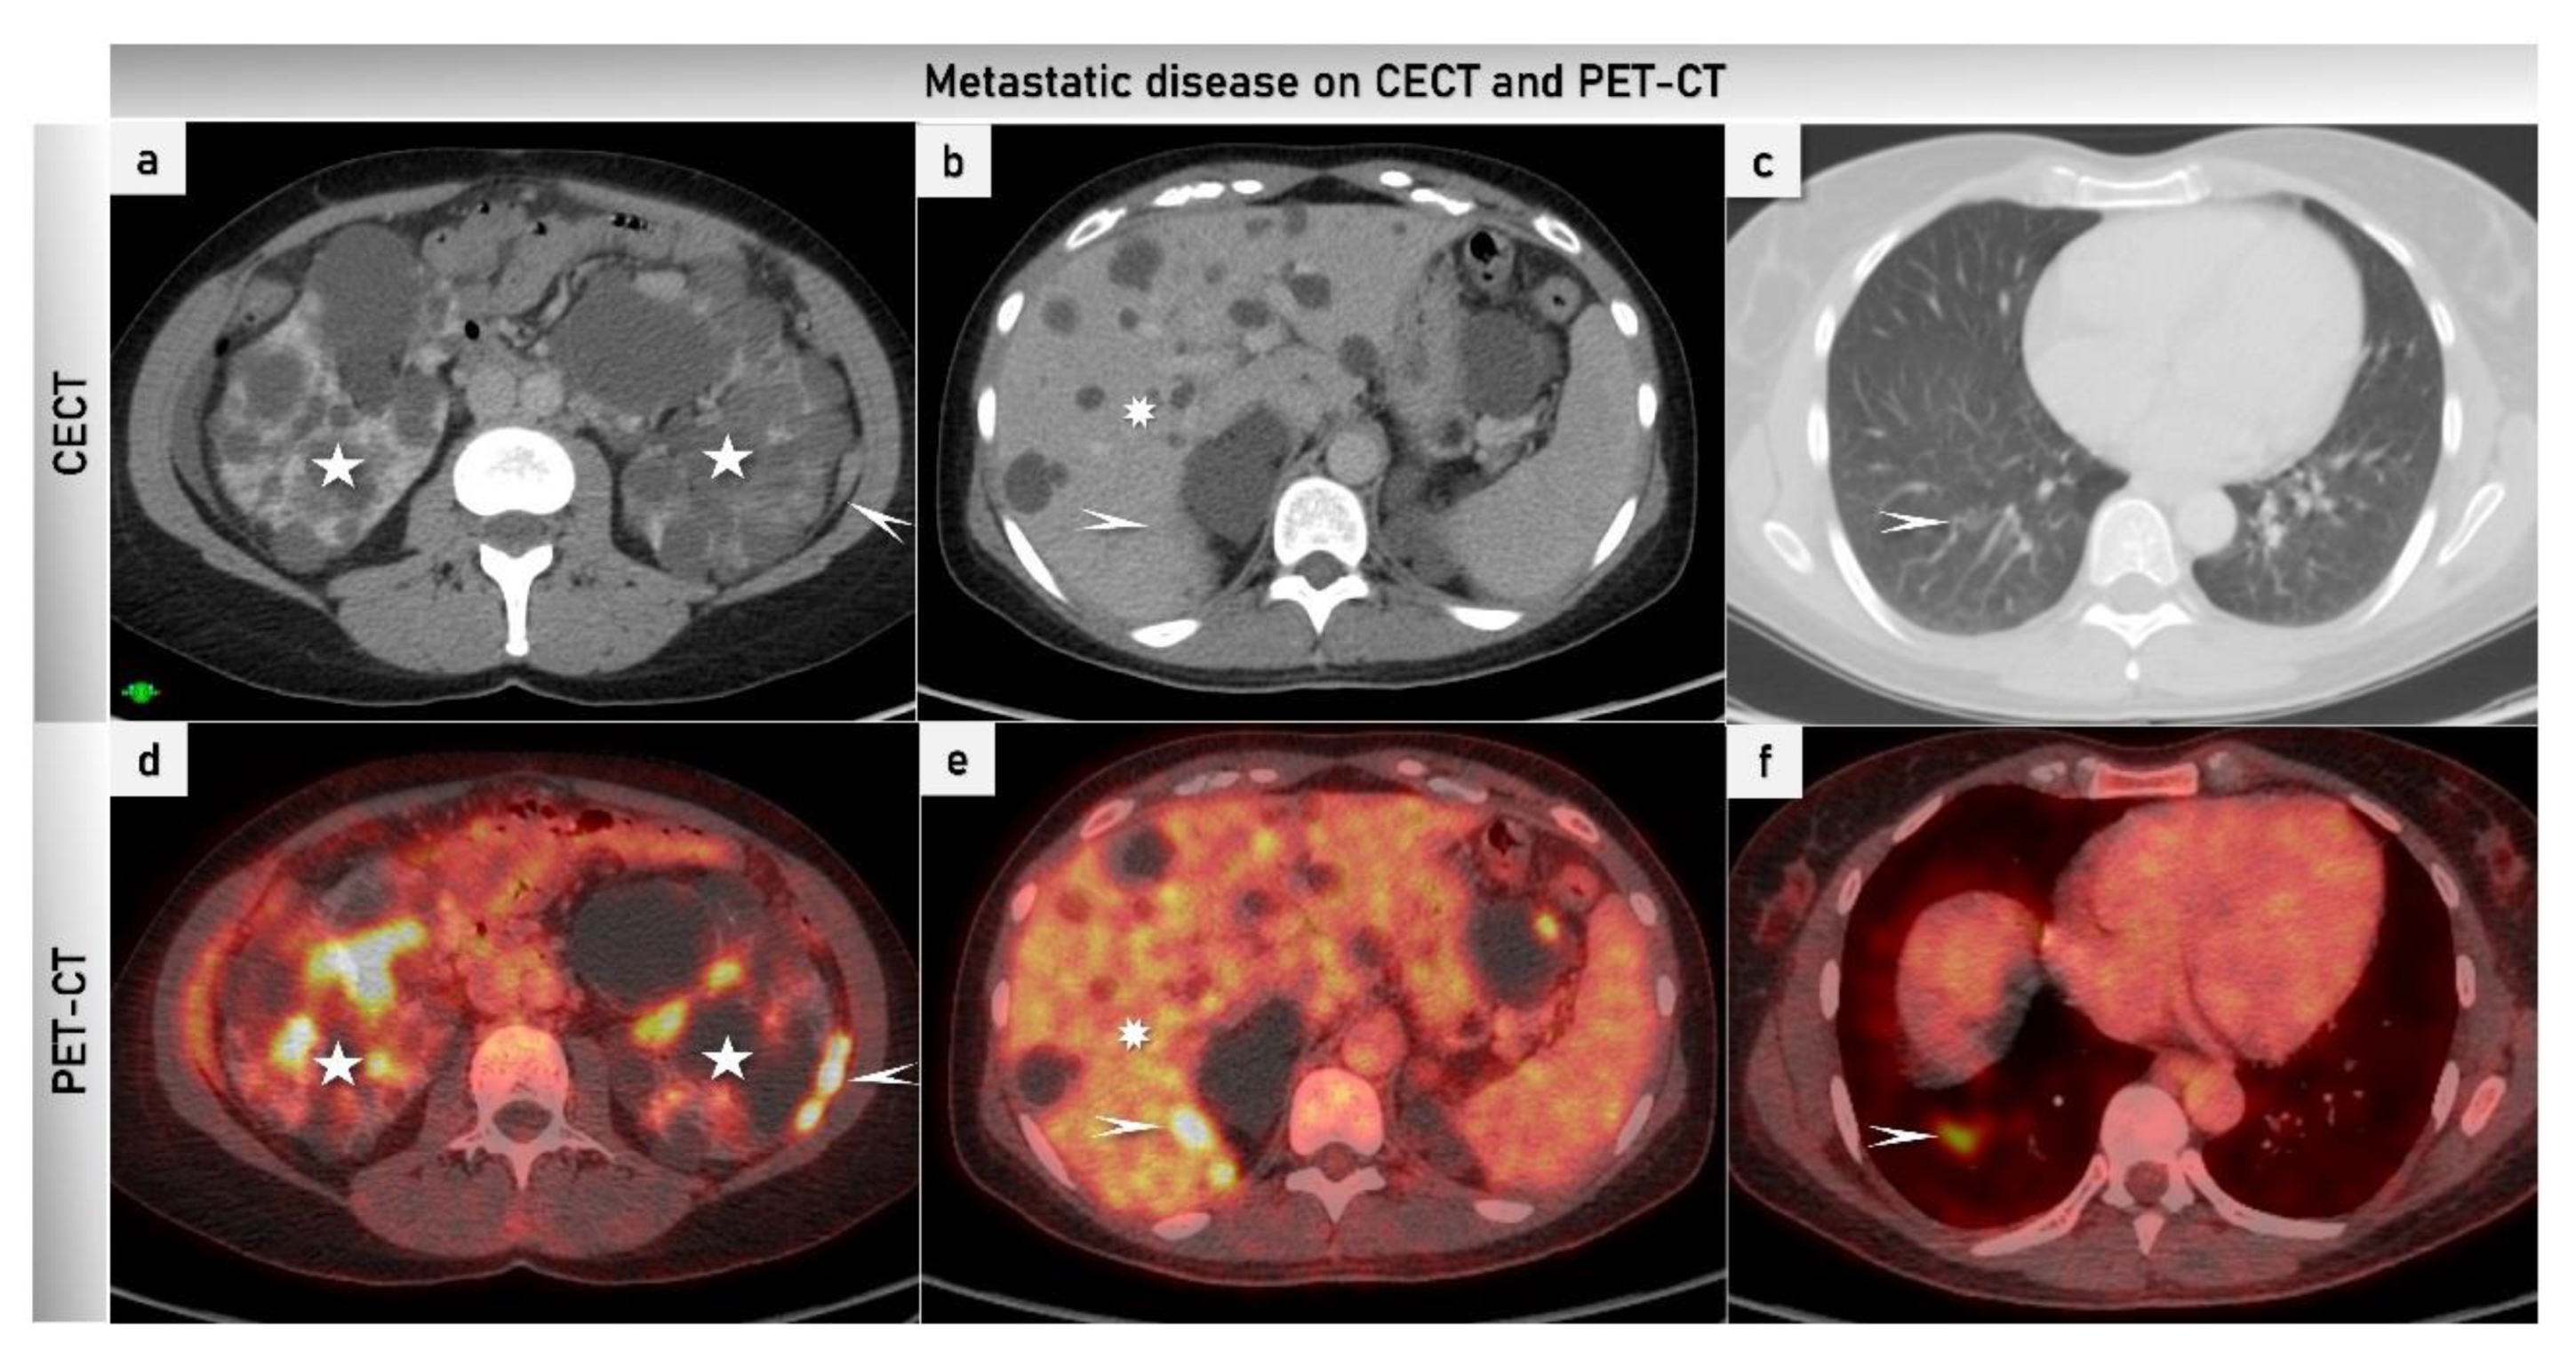

2.3.4. Positron Emission Tomography

- Nougaret, S.; Addley, H.C.; Colombo, P.E.; Fujii, S.; Al Sharif, S.S.; Tirumani, S.H.; Jardon, K.; Sala, E.; Reinhold, C. Ovarian carcinomatosis: How the radiologist can help plan the surgical approach. Radiographics 2012, 32, 1775–1800; discussion 1800-3. [Google Scholar] [CrossRef]